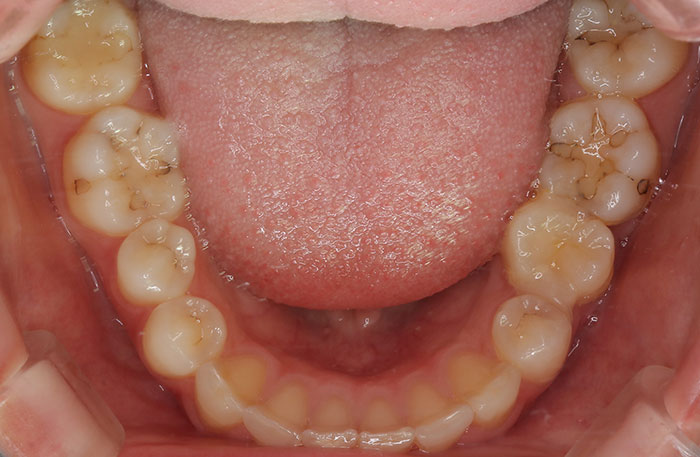

歯の移植の症例

Before

親知らずの歯を移植したケースです。患者様はとても喜ばれておりました。